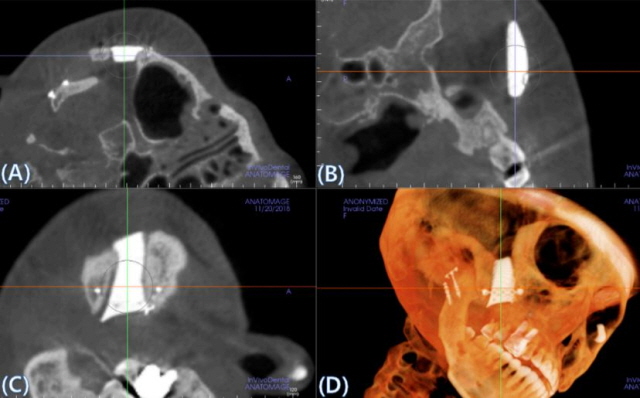

국내 의료진이 바이오세라믹을 이용한 3D프린팅 인공 광대뼈 이식의 재건 효과와 안전성을 입증했다./사진=이의룡 교수 논문 캡처

연구팀은 수술 6개월 후 CT 촬영을 통해 인공 광대뼈와 기존 뼈 사이의 골융합 및 고정상태, 만족도, 안전성 등을 평가했다. 그 결과, 인공 광대뼈의 골융합률은 100%로, 수술 직후와 비교했을 때도 뼈에 더 가깝게 부착된 것을 확인했다. 또한 수술 후 부작용도 나타나지 않았으며, 환자의 만족도 점수는 10점 만점에 9점이었다. 모든 환자는 심미적·기능적 측면에서 만족감을 나타냈다.

이런 문제를 해결하기 위해 금속 소재 보형물이 개발됐지만, 금속 소재라는 특성 때문에 CT 영상 촬영에 판독 정확도가 떨어진다는 단점이 있었다. 그러나 이번 임상에서 사용된 시지바이오의 제품은 뼈와 유사한 성분으로, 뼈와 직접 유합되는 고강도 생체활성 바이오세라믹 소재를 사용했다.

이의룡 교수는 “이번에 적용된 생체활성 바이오세라믹 소재는 영상학적 판독 정확도에 영향을 미치지 않는 소재”라며 “새로운 안면 뼈 재건 방법으로 환자 3D프린팅 바이오세라믹 소재의 안전성과 효과를 입증함으로써 광대뼈 결손에 대한 이식 재건뿐 아니라 안면기형, 두개골 결손 등 향후 다양한 이식 재건 치료에 적용될 수 있을 것으로 기대된다”고 말했다.